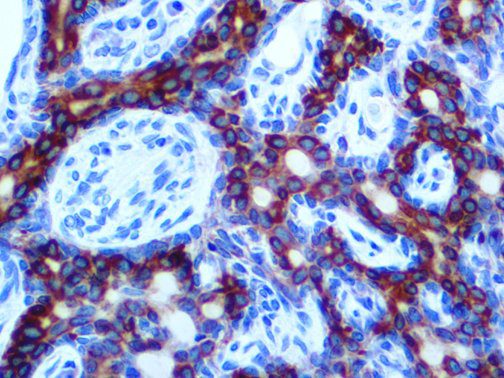

The first cytokines released are interleukin 1β (IL-1β) and tumor necrosis factor-α (TNF-α), which attract a variety of circulating white blood cells (WBCs) to the infection site, including neutrophils, monocytes, macrophages, and natural killer (NK) cells. This response, along with the antipathogenic chemicals released by these cells (i.e., complement), comprise the innate immune response. These cells directly attack the invading pathogen and also release additional cytokines, chief among them interleukin-1 and 6 (IL-6). IL-6 is essential for invoking the adaptive immune response, which calls T-cells, B-cells, and T helper (Th) cells to the infection site. IL-6 also stimulates further recruitment, proliferation and activation of macrophages.

It is the ICU physician who is most likely to witness one of the deadliest manifestations of the abnormal immunological response, the cytokine storm syndrome (CSS). This response is also referred to by some as the cytokine release syndrome (CRS). CSS is characterized by continuous activation and expansion of macrophage and lymphocyte populations, which secrete large amounts of cytokines, causing the cytokine storm. This massive cytokine release is akin to hemophagocytic lymphohistiocytosis (HLH) disease, a syndrome characterized by initial unchecked and persistent activation of cytotoxic T lymphocytes and NK cells.

This activation induces inflammatory monocytes to highly express IL-6, starting a localized and then systemic cascade effect that results in hyperproduction of IL-6, which accelerates the inflammatory process. Because IL-6 also increases vascular permeability, excessive levels cause blood vessels to become very leaky. This, along with clotting factors released from vascular endothelial cells, stimulates the coagulation cascade, resulting in microthrombosis (tiny clots), which leads to ischemia and tissue death of the kidney, intestines, heart, liver, brain and extremities.